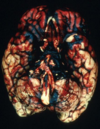

Subarachnoid hemorrhage

Caused by Berry aneurysm

What is this. What are the complications of this?

Berry aneurysm

Rebleeding

Vasospasm

Fibrosis of subarachnoid space